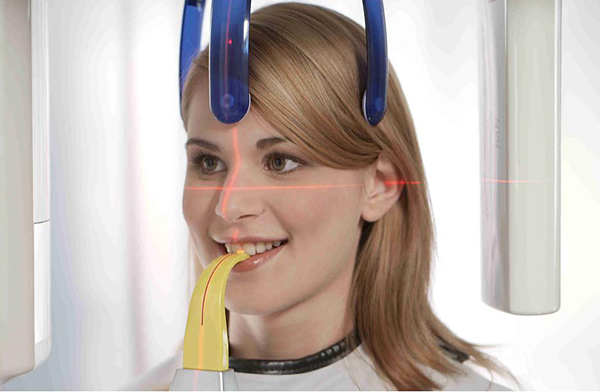

Фотографии и изображения КТ аппарата ORTHOPHOS SL

Раздел: Мудрость в фокусе